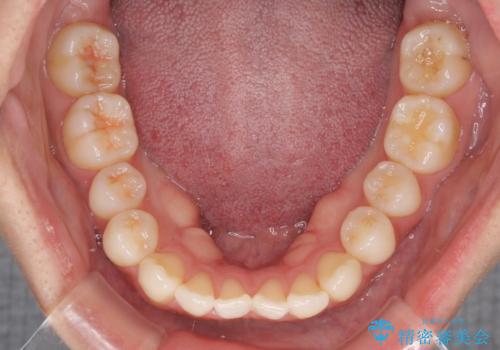

- 下唇に上の前歯が当たることを気にして来院された患者様です。

上顎の親知らずを抜去し、歯列全体を後方に移動させるとともに、IPR(歯と歯の間を削る)を行うことで口元の閉じにくさを改善していくこととしました。

咬合力が強く、マウスピースを介した咬み込みが顕著であったため、奥歯の咬みにくさやIPRのスペースが改善しにくく、治療期間が思った以上にかかってしまいました。